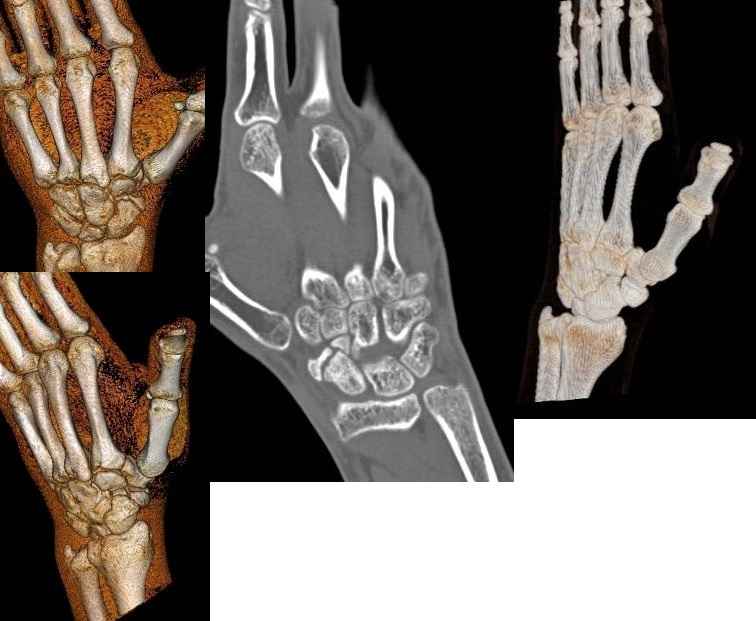

Обратился пациент с несросшимся переломом ладьевидной кости правой кисти

В нашу клинику обратился пациент 23 лет с несросшимся переломом ладиевидной кости правой кисти. Лечился он консервативно, в травм. пункте, результат неудовлетворительный. Хотелось бы выслушать Ваше мнение по поводу его дальнейшего лечения.